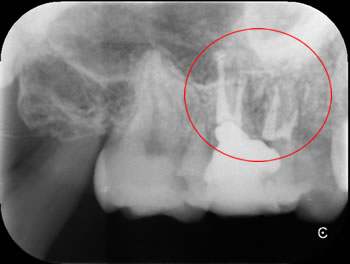

根管充填したところです。薬が4つはいっています。赤丸がMB2です。

根の本数は4本であることがわかります。白い薬が4つ見えますね。